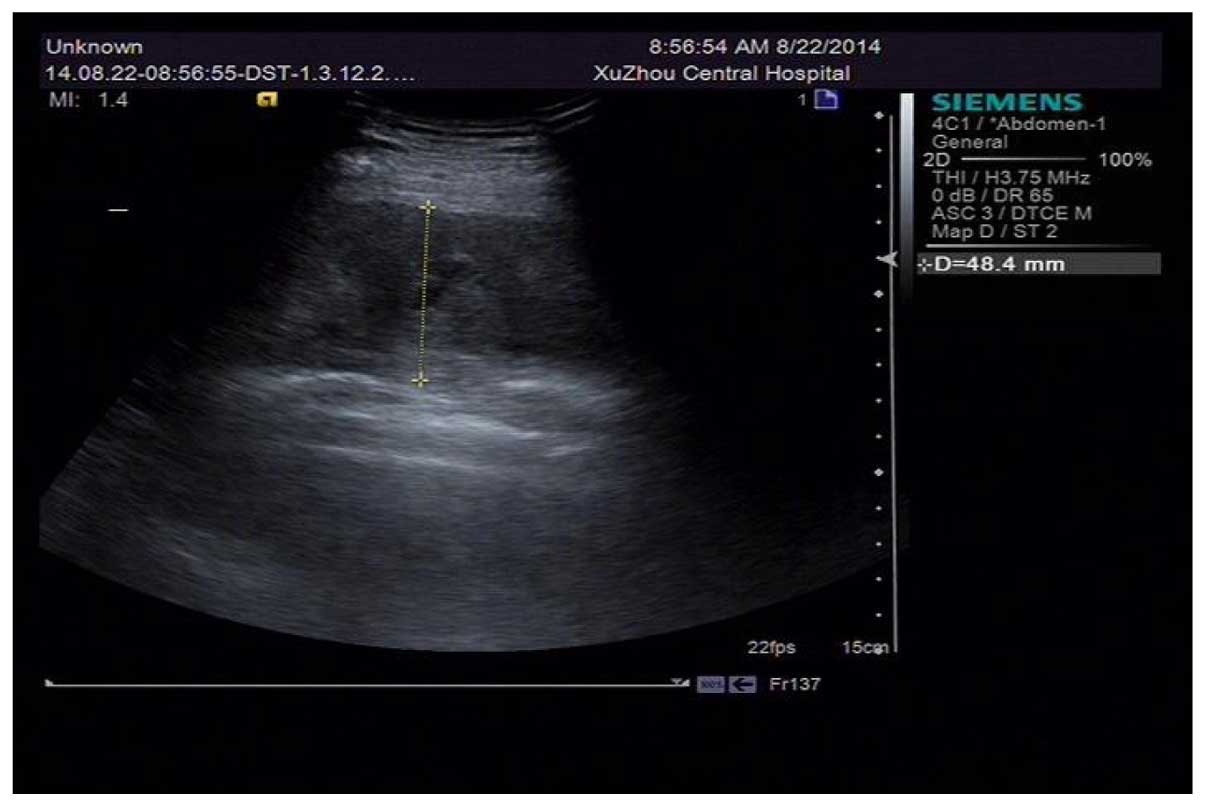

Spontaneous hematoma in the setting of dual anti-platelet therapy with ticagrelor: A case report

A 69-year-old male patient was admitted to hospital because a lump was discovered, accompanied with pain lasting 5 h under his right scapula. Two months earlier, he had undergone a double-stent insertion operation due to lesions on the end of the left main coronary artery, the opening of left circumflex artery, and the opening of the anterior descending branch. After the operation, he was administered with dual anti‑platelet therapy (DAPT) with aspirin and ticagrelor and was diagnosed with hematoma under his right scapula through ultrasonic inspection. It was established that no other factor, except DAPT, was responsible for his spontaneous hematoma.

Figure 1